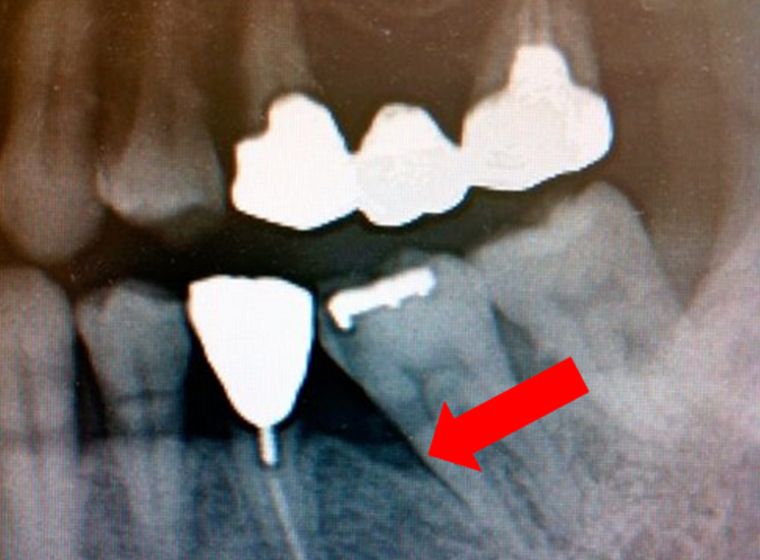

症例紹介

-

左の画像の矢印部分の黒影は、歯周病によって顎の骨が溶かされている状態です。治療から1年後の画像では影がなくなっており、顎の骨が回復していることが分かります。